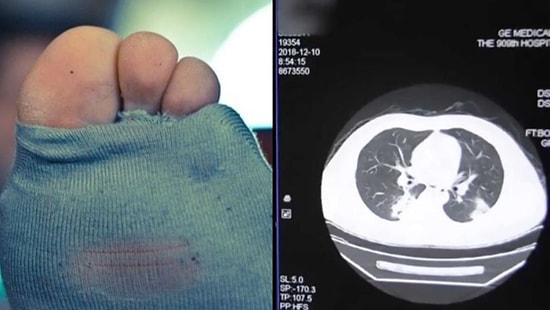

Güney Afrikalı yetenekli müzisyen Musa Manzini, geçtiğimiz günlerde beyninden bir ameliyat oldu. Cerrahi müdahale ile bir tümorün çıkarıldığı operasyonda daha çok filmlerde görebileceğimiz sahneler gerçekleşti! Genç müzisyen ameliyat masasında, gitarın tellerini tıngırdatmaya devam ediyordu! Bilimin bizi bir kez ağzımız açık bıraktığı olayın detaylarını ise LadBible'dan derledik.